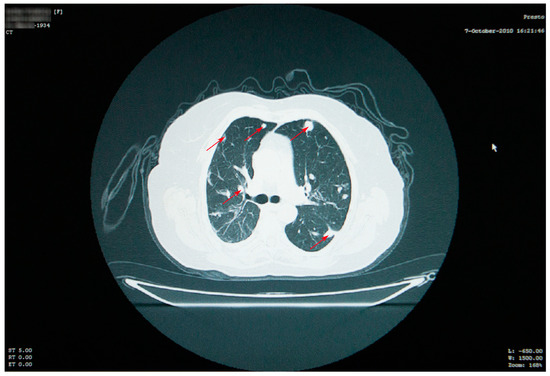

At her check-up in October 2006, the thoracic radiograph raised the suspicion of lung metastases from a cancer of unknown location (numerous 1–2 cm opacities, with bilateral lung dissemination) (Figure 1).

Thoracic and abdominal CT scans were performed, which revealed numerous thoracic masses, located in both the lungs and the pleura, round or oval in shape, centimetric or millimetric in size, with different consistencies, some liquid with calcifications, some condensed, sometimes clustering, as well as bilateral pachypleuritis, more pronounced on the right side (Figure 2).

Figure 2. Thoracic CT scan showing numerous thoracic masses (red arrows), located bilaterally, with different consistencies, and bilateral pachypleuritis.